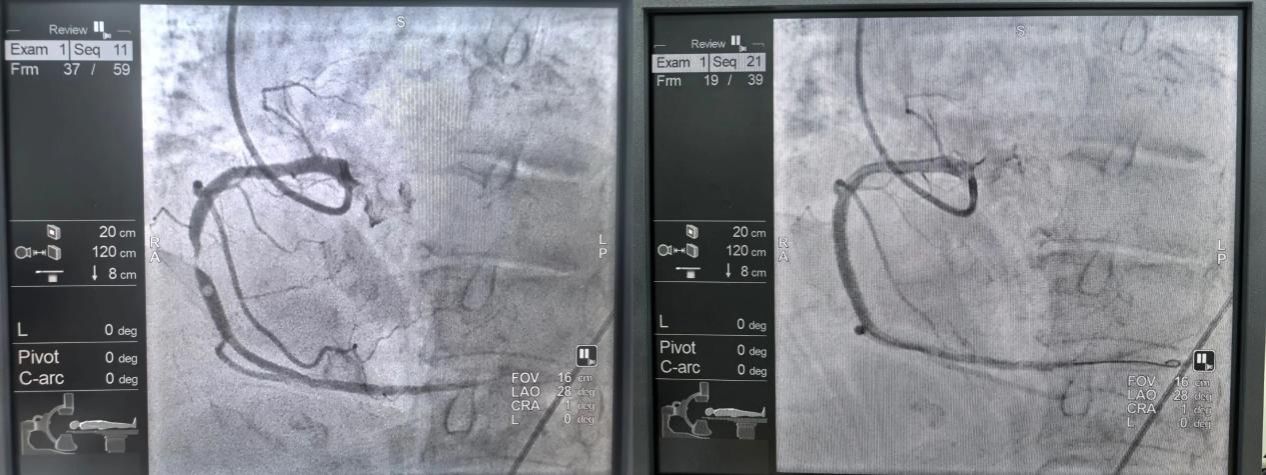

2、新疆医院介入诊疗中心持续开展疑难重症诊疗技术

新疆医院成功开展频发性室性早搏射频消融术,以精准微创的技术为患者重启了平稳的心律,展现了医院在复杂心律失常诊断与介入治疗方面的综合能力,标志着医院心律失常诊疗迈入精准介入治疗的新阶段。

新疆医院成功为一位90岁高龄的急性冠脉综合征患者实施急诊介入手术。针对患者超高龄、超高危的状况,以及复杂的血管条件—右冠开口变异、前降支完全闭塞、右冠狭窄达99%,团队经严谨评估,精心准备,精准植入支架,此次超高难度手术的成功,标志着医院在急危重症及复杂冠心病诊疗领域实现了重要突破。